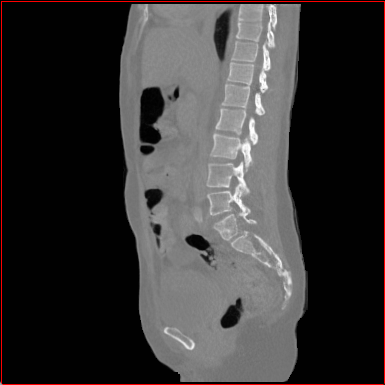

Figure 2: Qualitative comparison across axial (top row), sagittal (middle row), and coronal (bottom row) views. Columns correspond to different methods. MAISI-DDPM and MAISI-v2 in this figure are unconditional synthesis which do not use ControlNet or segmentation maps.

Qualitative Evaluation:

Figure 2 presents representative slices from the axial, sagittal, and coronal planes. GenerateCT (hamamci2024generatect) is a 2D model, so it lacks inter-slice consistency, leading to poor image quality in the sagittal and coronal views. MedSyn (xu2024medsyn) produces noticeably blurry results with mosaic-like artifacts, such as region inside the red box. HA-GAN (sun2022hierarchical) generates visually sharp images but with mosaic-like artifacts, such as region inside the red box. Also, its voxel spacing is not available, which limits its applicability in real-world medical imaging tasks. Moreover, all three methods are restricted to synthesizing small anatomical regions. In contrast, both MAISI and MAISI-v2 are capable of generating high-quality 3D volumes that span larger body regions while preserving fine anatomical details and realistic structure.